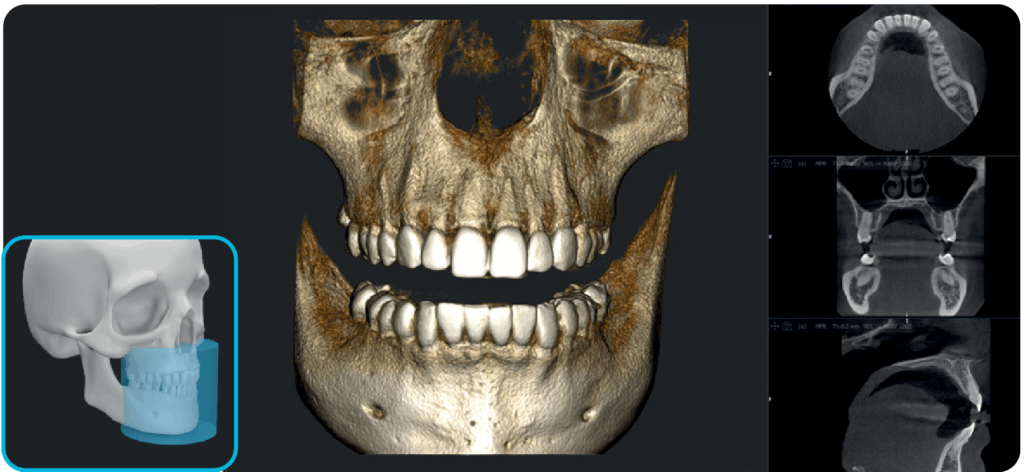

NOWOŚĆ FOV 17×12 cm

Idealne rozwiązanie dla skomplikowanych przypadków ortognatycznych, planowania implantów jarzmowych i chirurgii ortodontycznej.

X-MIND® optima łączy zaawansowaną technologię sprzętową z oprogramowaniem nowej generacji RealGUIDE 5.4, wprowadzając zalety sztucznej inteligencji do każdego etapu opieki nad pacjentem.

Oprogramowanie RealGuide 5.4 wykorzystuje technologię AI, aby maksymalnie ułatwić i usprawnić pracę lekarzom na każdym etapie leczenia implantoprotetycznego, zapewniając lepszą komunikację z pacjentami, budując zaufanie i poprawiając wskaźniki akceptacji leczenia.

Upraszczając złożone zadania i automatyzując kluczowe procesy, oprogramowanie usprawnia cały proces, umożliwiając szybsze i dokładniejsze planowanie leczenia.

Segmentacja zębów

Segmentacja kości

Pozycjonowanie implantu

Projektowanie uśmiechu